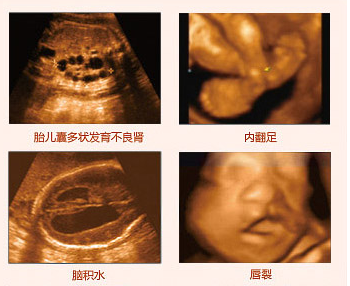

因為畸形兒對大多數(shù)家庭來說都難以接受這個事實,令親人難以相信,而且這種情況越早進行干預對孕婦的身體以及家屬的心理影響會越小。而四維彩超作為目前上進的彩色超聲檢查設備,具備較強大的排畸功能,對胎兒大體的畸形:如唇裂、腭裂、骨骼發(fā)育異常等能早期診斷。莆田盛興醫(yī)院引進美囯先進的GE四維彩色超聲設備,是莆田準媽媽做好胎兒排畸較關鍵的一步。

據(jù)醫(yī)生介紹,較易致胎兒畸形的外因有病毒、射線、 物等,內(nèi)因則與遺傳因素或染色體的異常有關。而同其它超聲診斷過程相比,四維彩超可以實時的觀察人體內(nèi)部器官的動態(tài)運動。臨床醫(yī)生和超聲科醫(yī)生可以檢測和發(fā)現(xiàn)各種異常,從血管畸形到遺傳性綜合征。四維彩超能夠多方位、多角度地觀察宮內(nèi)胎兒的生長發(fā)育情況,為早期診斷胎兒先天性體表畸形和先天性心臟疾病提供準確的科學依據(jù),以便盡早發(fā)現(xiàn)寶寶是否存在這樣的不良情況,能使媽媽生個聰明健康的小寶寶。推選閱讀 傳統(tǒng)b超胎兒產(chǎn)后畸形 莆田盛興醫(yī)院四維彩超成較

在四維彩超胎兒篩畸檢查中,首先要篩查的是頭顱畸形,看胎兒是否是無腦兒、腦積水、小頭畸形。如果早四維彩超檢查中,發(fā)現(xiàn)胎兒發(fā)育存在異常,可以對有嚴重畸形的胎兒在產(chǎn)前做出診斷,對發(fā)現(xiàn)有輕微異?;蚩梢僧惓5奶海山o予密切追蹤觀察,為臨床提前干預、早期處理提供建議。推選閱讀 四維彩超對肚中寶寶會有影響嗎